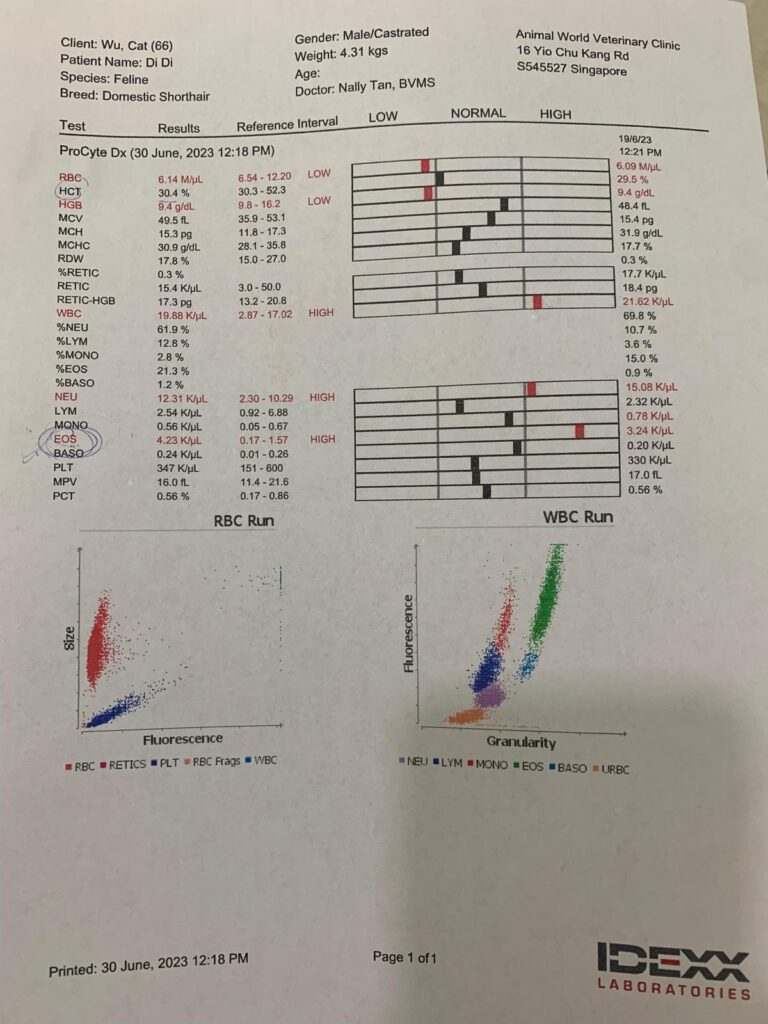

Morning: bring didi go dr nally review. 4.28kg – lose 60g in 2 days. Cbc taken. HCT up to 30.4%, EOS even higher. Reject doing liver panel. Nothing significant. Just tell me to finish up the 14 days Clav then can stop (till 2.7) Drontal n review every 2-3 months. I’ll decide again Re the allergy jabs.

HCT 29.5%, dr nally say she don’t like her EOS 3.24, but it’s a gone down figure cos March he had fenbendazole alr. Will tell them deworm him today. Alt 177 – continue ornipural. GGT 6, restart ursofalk 65mg. 15mg/kg in short. add on Clav 14 days, 0.22ml and anti histamine jabs (expire dec 23) – price $188 don’t make sense so didn’t buy.

Cbc Chem10 done. His blood is soooo dark red. yet 29% only!?

HCT 29.2% – monitor le. Alt 216. Think ornipural working ok for him – continue, dr Brandon says that’s what he use last time like a supplement so no harm giving.

Cbc out: Eos high again – dr wants him to be dewormed. Hct 26.9%, going up, wbc 20.35 going down doxy to continue for total 21 days.